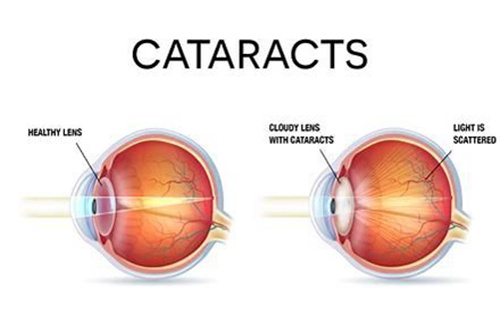

普瑞眼科在济南的口碑一直不错,尤其是其引进的德国蔡司三焦点晶体技术,能帮助老年人一次性解决白内障和老花眼问题。

三焦点晶体:相比传统单焦点,可同时优化远、中、近视力,术后不用戴老花镜。

严格术前评估:确保患者符合手术条件,降低术后眩光等风险。